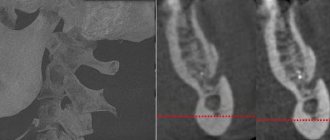

Рекомендуется консультация нейрохирурга, магнитно-резонансная томография забрюшинного пространства.